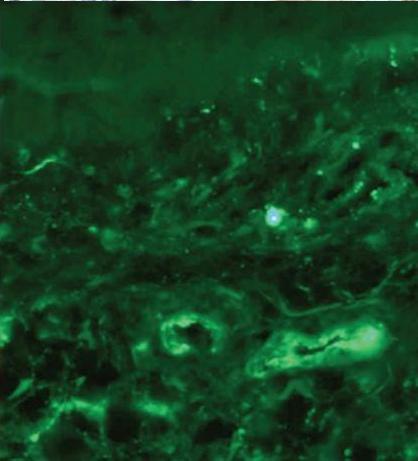

- Immunofluorescence: Identifies IgA deposition in small vessel walls, along with C3, fibrin, and IgM.